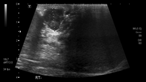

Massive retroperitoneal dedifferentiated liposarcoma in a young patient

Fernando X Moyon and others

Journal of Surgical Case Reports, Volume 2018, Issue 10, October 2018, rjy272, https://doi.org/10.1093/jscr/rjy272